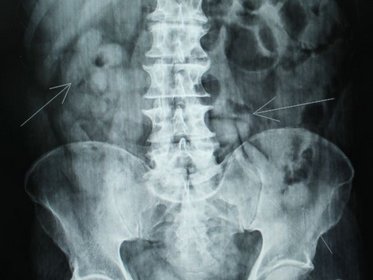

Paciente internada é suspeita de ter engolido droga para fugir de flagrante

Para o azar da vítima durante os procedimentos de atendimento ela foi submetida a exame de raio-x, sendo detectados vários pontos com formatos estranhos no seu aparelho digestivo, o que despertou a suspeita  dos objetos serem embalagens contendo droga que ela poderia ter ingerido para transportá-las.

A Polícia Militar foi comunicada da suspeita e passou a fazer a escolta da paciente que permaneceu no hospital em observação. Durante toda esta quarta-feira (12) foram feitos os procedimentos de lavagem estomacal e intestinal para que os corpos estranhos fossem expelidos, porém sem sucesso; chegando a ser cogitada uma intervenção cirúrgica, o que foi descartado ao longo do dia.

Até o fechamento desta edição por volta de 19h10min, a paciente seguia internada no hospital com acompanhamento clínico sobre escolta policial.